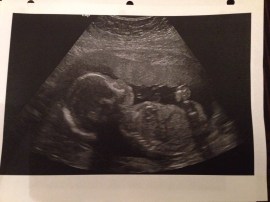

Robyn was 22 weeks pregnant when she suffered a cerebral hemorrhage on Dec. 28, 2013. The damage was irreparable, and she was declared brain dead the next day. Doctors are now trying to keep her alive for seven more weeks, until the fetus is 34 weeks old and has a better chance of surviving outside the womb.

Dylan took a leave from work and is now preparing for the baby, who has been named Iver Cohen Benson. Friends, family and strangers in Victoria have been rallying around him. Donations are being taken for the family on a website called the “Baby Iver Fund” .